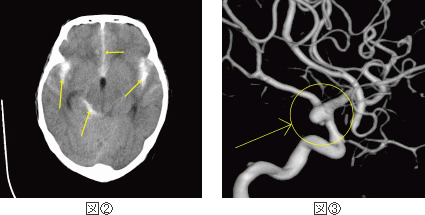

くも膜下出血の急性期看護。

くも膜下出血の原因メディカルノート。

くも膜下出血とは東京銀座の脳梗塞・脊髄損傷クリニック。

くも膜下出血とは北青山Dクリニック キレーション療法部門。

脳幹出血福岡の脳神経外科 - はしぐち脳神経クリニック。

くも膜下出血の症状・5つの前兆をチェック健診会東京メディカルクリニック,夜間診察も。

くも膜下出血についてくも膜下出血の症状と治療法 横浜新都市脳神経外科病院。

脳卒中 くも膜下出血 の原因究明をめざして - 研究へのご協力のお願い。

脳出血について脳出血の症状と治療法 医療法人社団 明芳会 横浜新都市脳神経外科病院。

脳出血・くも膜下出血循環器情報サイトAssist。

くも膜下出血の前兆・原因・症状 漫画でわかる 横浜もえぎ野クリニック 脳神経外科・脳神経内科横浜市・青葉区・青葉台。

危険な病気 くも膜下出血の治療・予防病気と治療の検索サイト「メディカルブレイン」。

三種類の予防対策を日常に取り入れてくも膜下出血を防ぐ 脳梗塞・脊髄損傷後遺症の幹細胞治療ニューロテックメディカル。

くも膜下出血 - とくなが内科胃腸科外科クリニック熊本市 東区 内視鏡胃カメラ 大腸カメラかかりつけ医。

くも膜下出血の死亡率について再生医療脳梗塞・脊髄損傷の幹細胞治療ニューロテックメディカル。

くも膜下出血について - 脳梗塞・脊髄損傷クリニック。

くも膜下出血とは症状、検査、治療について千葉西総合病院。